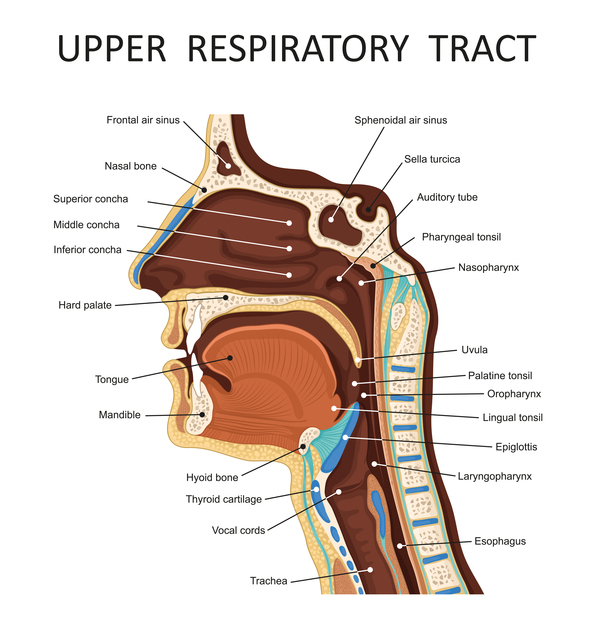

喉頭とは、咽頭と気管の狭間で、舌骨より下に位置し、気管より上に位置している頸部中央に一つ存在する器官のことを指します。

体の表面でいえば、喉仏として触れることができ、嚥下する際に時には上前方に動きます。喉頭には、嚥下時の誤嚥の防止や発声等の機能を司っています。

喉頭は、呼吸をする際に空気が出入りする管と考えられ、その下方が気管となり、肺に繋がっています。更に喉頭と気管の後方には食道があり、咽頭と胃を繋いでいます。

頸部を外からみると、男性では喉仏が目立っており、この部分は喉頭を形成する軟骨のうち、いちばん大きな甲状軟骨の前上端部にあたり、更に少し下方の内側に声帯が位置しております。

声帯は喉頭という管の左右の壁から突出した一対のヒダ状の構造で、呼吸をする際に左右に開いて空気を通し、声を出すときには中央に寄ってきます。